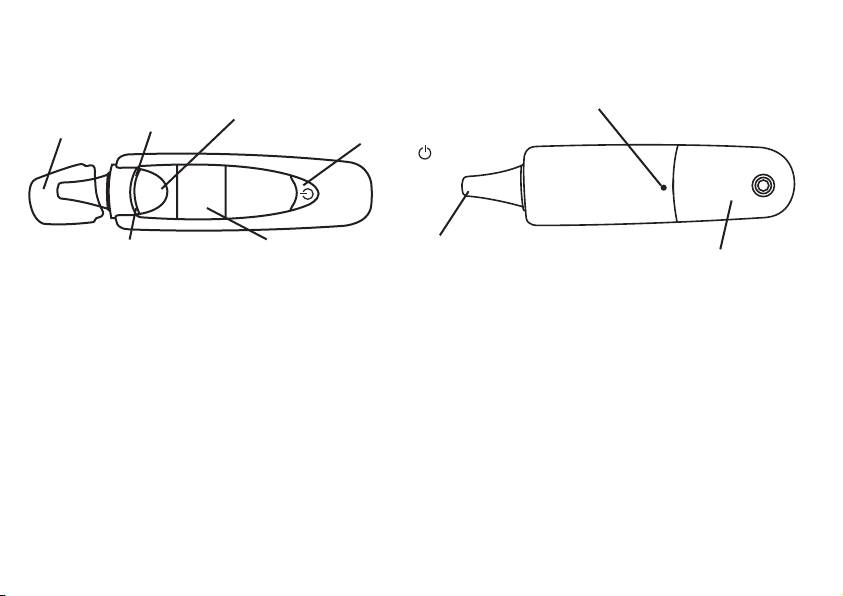

3. Descrizione dell’apparecchio

Lato anteriore

Dietro

Sblocco del vano batterie

LED rosso

Tasto di misurazione “SCAN“

Cappuccio

(allarme febbre)

protettivo

Tasto ON / OFF /

Memoria

SCAN

Punta del

LED verde

Display LCD

sensore

Coperchio vano batteria